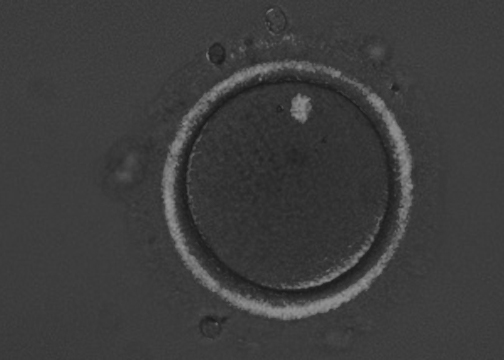

Zona imaging using birefringence on oocytes (an immature ovum or egg cell) to select the ones with highest chances of successful pregnancy.

Birefringence is the optical property of a material and is widely used in medical imaging.